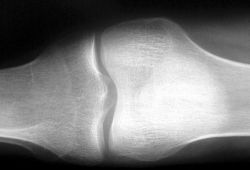

Reumatoidná artritída

Reumatoidná artritída (RA) je chronické zápalové ochorenie, ktoré sa prejavuje najmä postihnutím kĺbov, z toho pochádza aj jej názov artritída (arthritis – zápal kĺbu). Okrem kĺbov postihuje chorobný proces aj svaly a ich šľachy, väzy, teda najmä pohybové ústroje